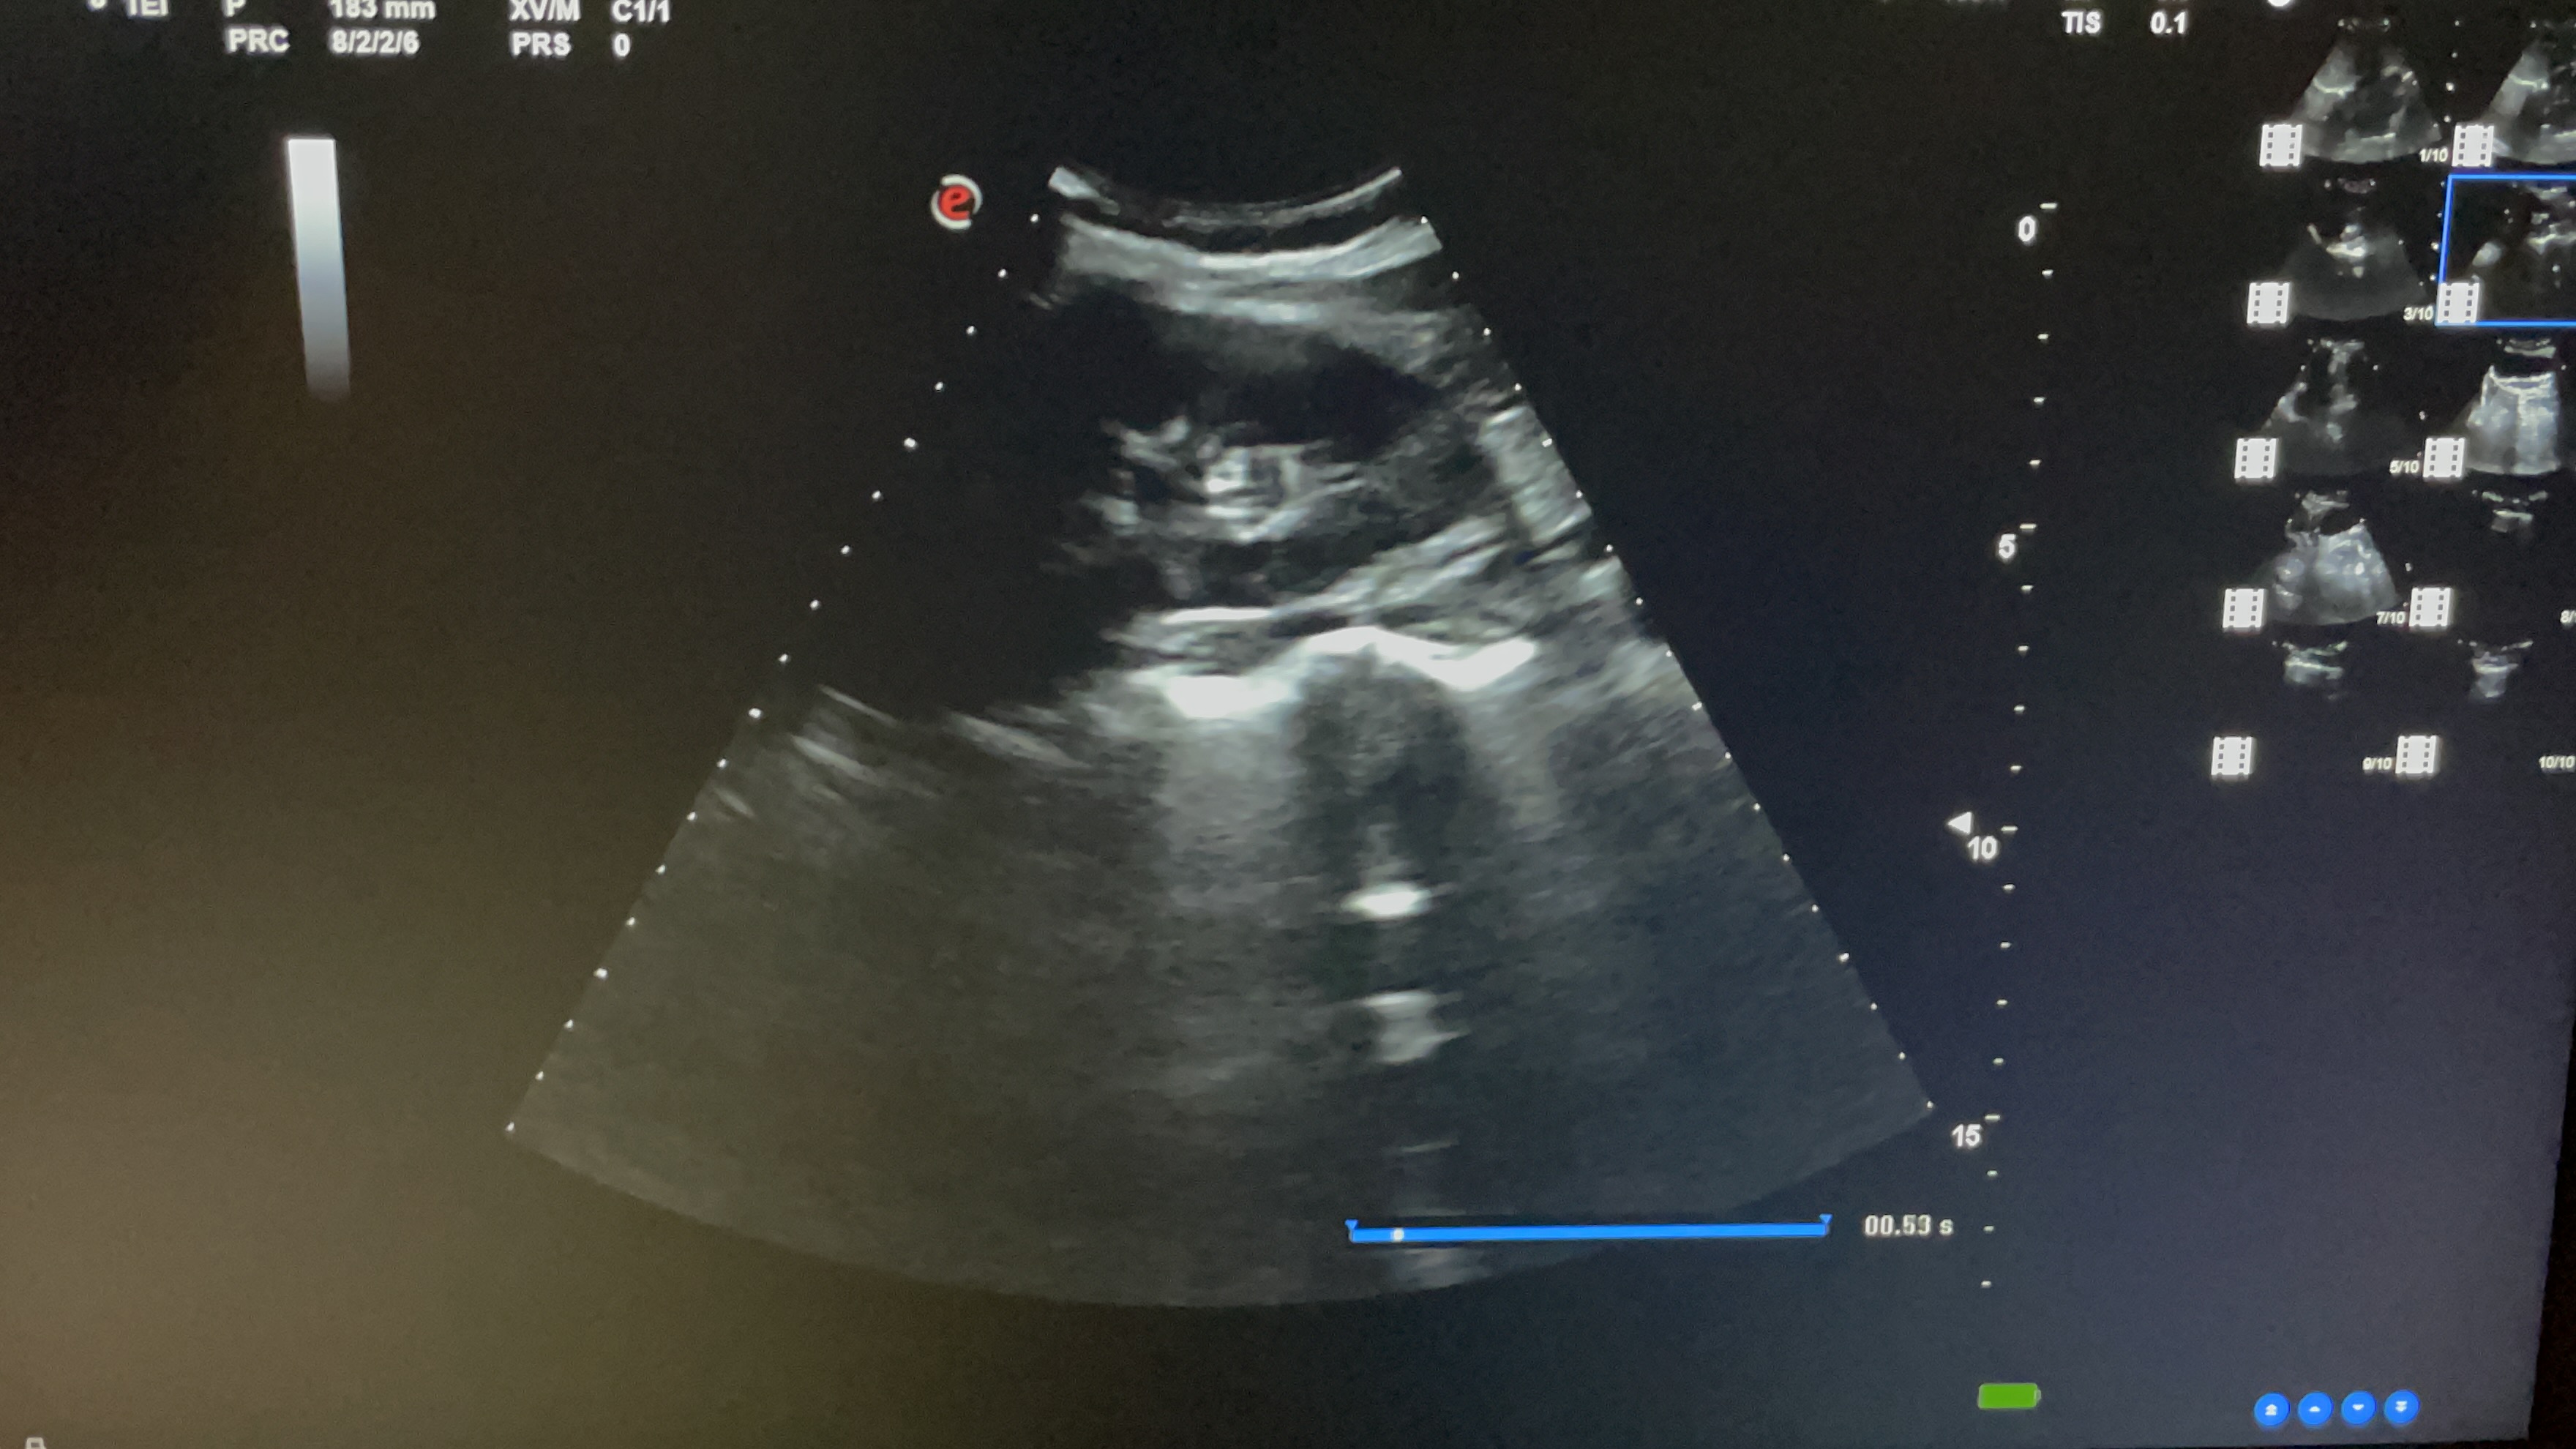

Estudio ecográfico con sonda abdominal de baja frecuencia, siguiendo protocolo ECO-FAST. Se explora región subxifoidea sin apreciarse presencia de líquido en saco pericárdico. Hipocondrio derecho libre de líquido en espacio de Morrison. Hipocondrio izquierdo sin presencia de líquido en espacio esplenorrenal. Imagen de región supra púbica, corte longitudinal y transversal donde no se observa líquido libre en saco de Douglas.

La exploración ecográfica de urgencias resulta de elevada utilidad. En un caso como este, de emergencia vital, nos permite realizar un amplio diagnóstico diferencial en los primeros minutos de atención médica, descartando la presencia de hemorragia abdominal (primera sospecha diagnóstica). Así, nos aporta información imprescindible en la toma de decisiones terapéuticas.